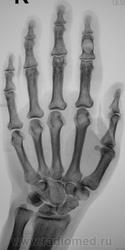

"Пальчик"...

Аневризматическая костная киста. Жалобы есть?

Энхондрома

Туберкулёзный остит средней фаланги 2 пальца.

В дифф.ряд-spina ventosa tuberculosa.

А вот здесь очень близко к костной кисте. Увеличение объема (вздутие), тонкий ободок (стенка) с четкими контурами, содержимое однородное. Даже дифряд строить не хочется.